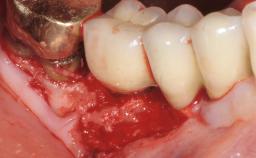

Ridge Preservation and Implant Placement for a Fixed Dental Prosthesis After a Car Accident

It is well known to clinicians that any removal of teeth will, over time, cause the dimensions of the alveolar ridge to be reduced by resorption of the bundle bone and by changes related to external modeling. This development is particularly evident in the crestal region with its thin buccal bone that consists of bundle bone almost entirely. The facial bone will rapidly resorb as blood supply from the periodontal ligament gets disrupted (Araújo and Lindhe 2005). There is no reason why traumatic tooth loss should not have the same consequences. It takes more than achieving implant osseointegration for a treatment outcome to be considered successful. No deficiency of bone or soft tissue is acceptable when an ideal esthetic outcome is the goal. Several articles (Sanz and coworkers 2011; Vignoletti and coworkers 2011) have reported on techniques of improving the alveolar ridge for implant treatment, notably focusing on protecting tissues from resorption.

Bone Augmentation Horizontal|Simultaneous|Sinus Floor Elevation|Staged

Augmentation Materials Xenogenous|Membrane